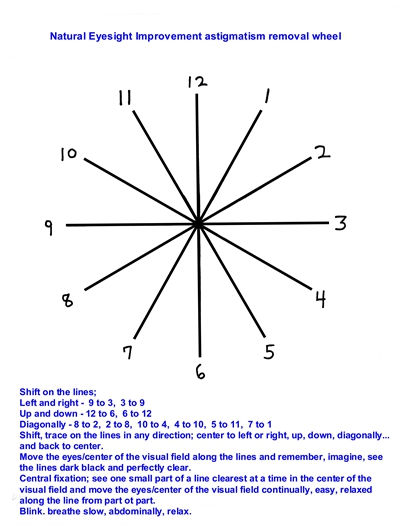

散光圖片

A:判斷自己有沒有散光,最簡單的方法是使用散光表來測試。散光表是一種簡單、方便的方法,但是它的準確度不是特別精確。在配鏡的情況下一般再用裂隙法,或者是交叉圓柱鏡法來精調散光的度數。散光表在網上可以看到,它類似於鐘錶的盤面,有12個數字。各個鏡線……